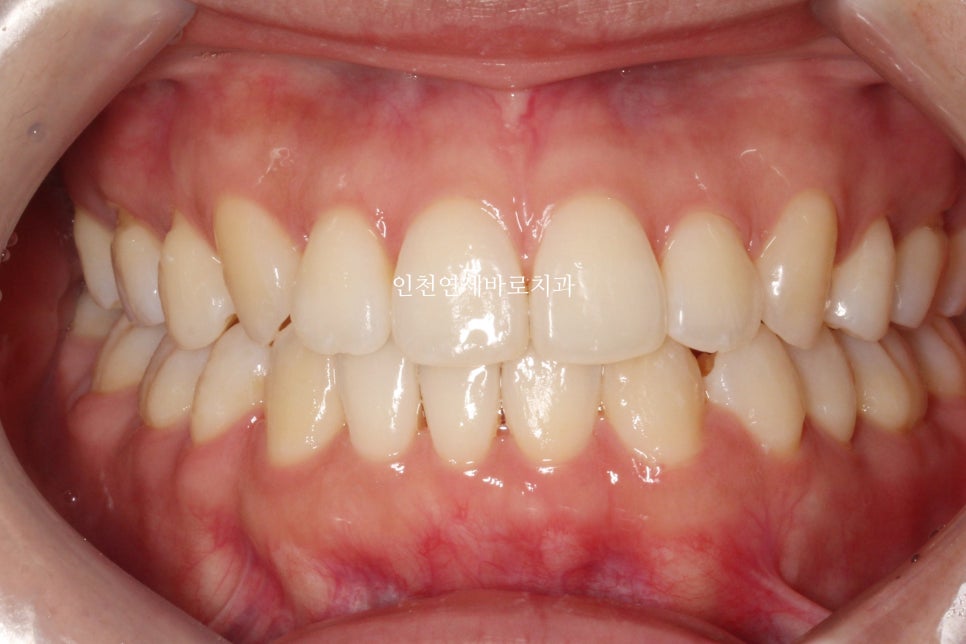

처음과 비교하여 안정적인 교합이 형성되었고 배열도 괜찮았기에 그만둘까도 고민했지만, 중심선이 안맞습니다.

#결손치아 가 있기 때문에 안맞는것이 당연하지만

맞추면 좋죠.

위쪽 중심선은 얼굴중심선과 맞는 상황.

아래와 위. 치아의 중심선을 맞추는 것이 우리의 치료 목표입니다.